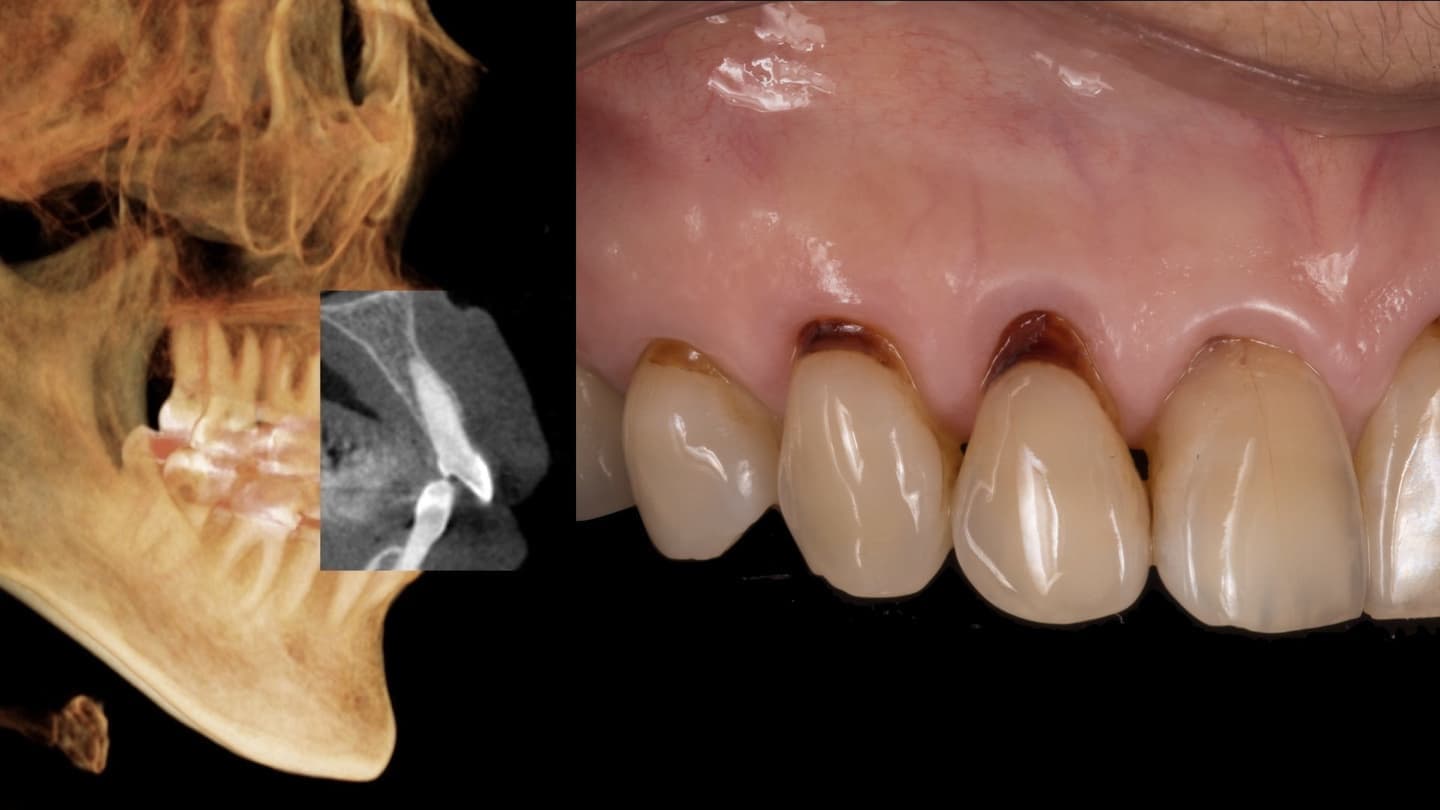

正確な診断を行います

全ての治療は診断からスタートします

あらゆる検査からの情報を分析します

基本的な検査だけでなく、CT検査、歯周病に特異的な細菌のPCR検査、噛み合わせの検査、生活習慣の見直しなどを行います

他院では見逃してしまうケースもしっかり対応します